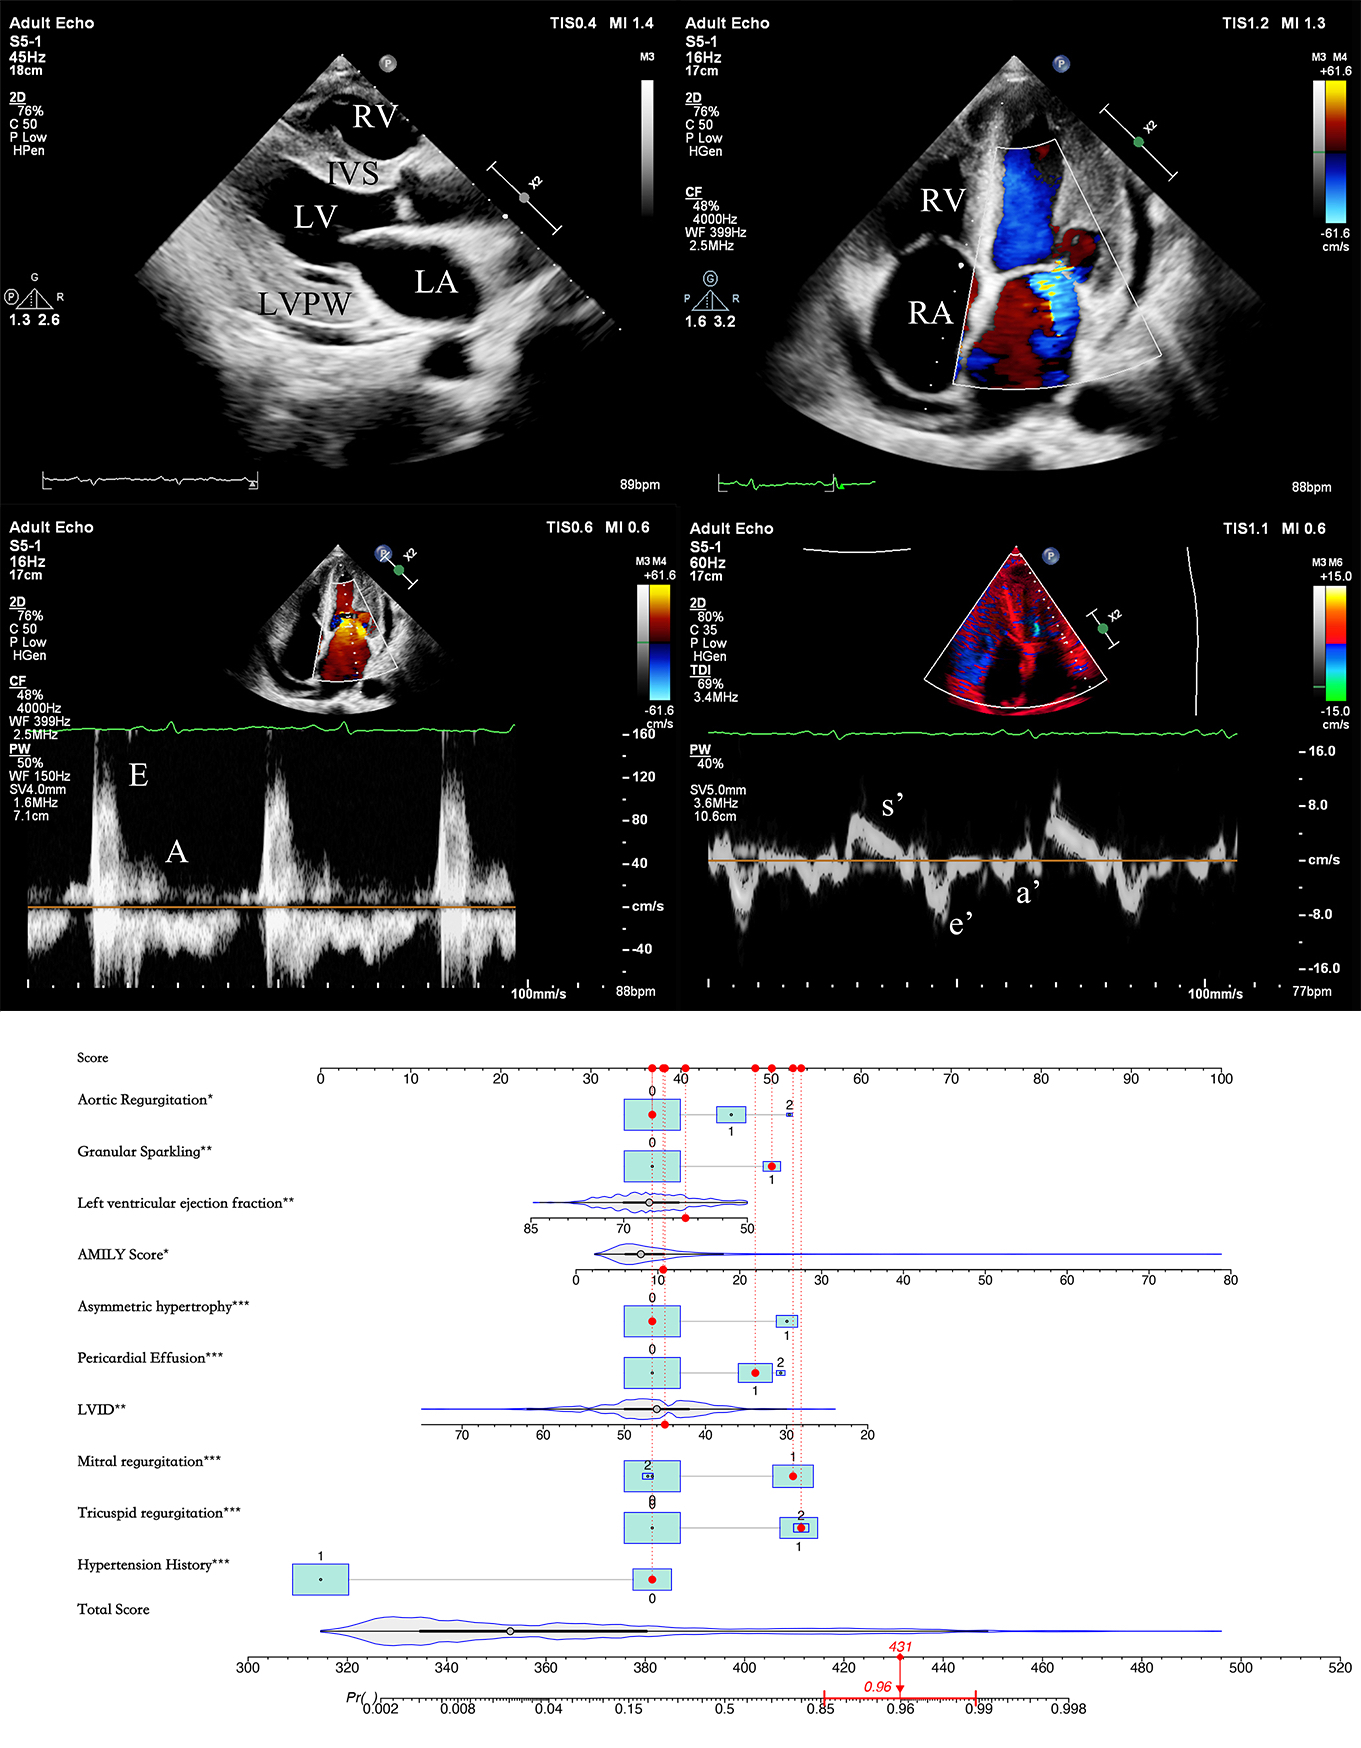

Development and Validation of an Echocardiographic Nomogram for Identifying Cardiac Amyloidosis in Patients with Left Ventricular Hypertrophy

Results: A total of 185 CA patients who underwent 309 echocardiography examinations with 1,213 echocardiographic data points from in-hospital non-CA-LVH cases matched for age, gender, and body surface area were included. Multivariable logistic regression analysis identified a history of hypertension [odds ratio (OR): 0.04, 95% confidence interval (CI): 0.021-0.073], left ventricular internal diameter in diastole (LVID) [OR: 0.927, 95%CI: 0.878-0.977], left ventricular ejection fraction (LVEF) [OR: 0.95, 95%CI: 0.908-0.993], AMYLI score [OR: 1.088, 95%CI: 1.024-1.161], asymmetric hypertrophy [OR: 3.729, 95%CI: 1.884-7.441], granular sparkling [OR: 3.111, 95%CI: 1.355-7.431], mild pericardial effusion [OR: 2.77, 95%CI: 1.563-4.937], mild aortic regurgitation [OR: 2.353, 95%CI: 1.278-4.361], mild mitral regurgitation [OR: 4.331, 95%CI: 2.347-8.141], and mild tricuspid regurgitation [OR: 3.837, 95%CI: 2.026-7.358] as independent predictive factors for CA in LVH patients. The constructed nomogram model demonstrated high accuracy (0.91-0.92), specificity (0.91-0.92), sensitivity (0.90-0.91), positive predictive value (0.73), negative predictive value (0.93-0.98), and Youden index (0.81-0.83).

Conclusion: The developed nomogram displayed remarkable predictive accuracy, which has the potential to enhance CA screening via routine echocardiography and strategically guide subsequent diagnostic evaluations.